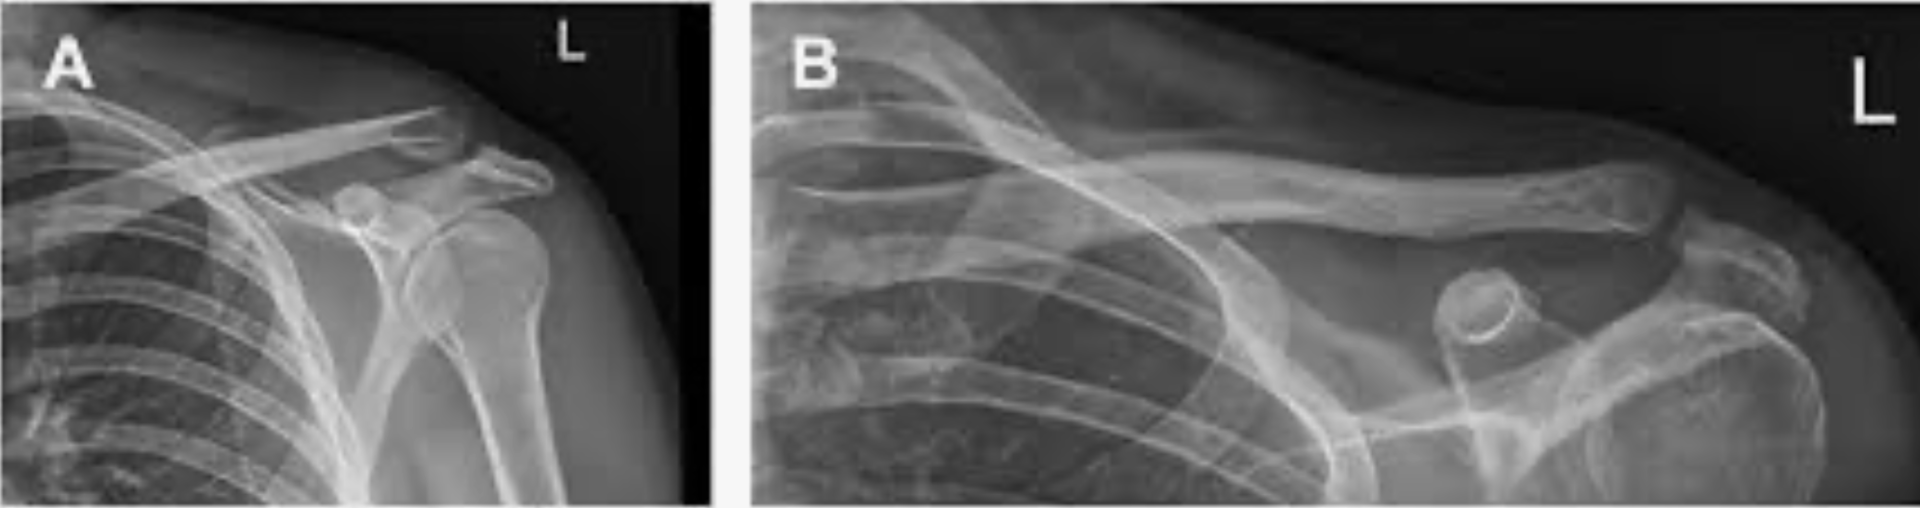

また, 大腿骨頚部骨折に対して人工骨頭挿入術が行われて, リハビリテーション中の高齢の患者さんが, 今日の2時頃にベッドサイドで転倒されてから, 手術をしていない反対側のふとももを痛がっていると夜勤の看護師さんから報告されたので, 診察しました. 痛い方の股関節を自分で動かすことはできましたが, 深く曲げるとふとももの付け根の痛みが出るので, 自分と同じく非転位型の大腿骨頚部骨折を疑いました. X線写真を撮像するようにオーダーを入れました.

同じように大腿骨頚部が外反陥入した骨折でした.

また, 大腿骨人工骨頭挿入術後の高齢患者さんの股関節のX線写真を見たところ, 反対側の大腿骨頚部に自分が受傷したのと同様の外反陥入型の骨折を認めました. ご家族に電話をして, 状況を報告しました. 学会で出張中の後輩医師が主治医となっているので, 出張から戻ってきた後に治療方針(手術しないで安静を保って骨がつながるのを待つか, 手術療法を行うか, 手術を行うとすると, 骨を器械でつなげる手術(内固定術)か人工骨頭挿入術か)を決定して, また連絡することになりました.